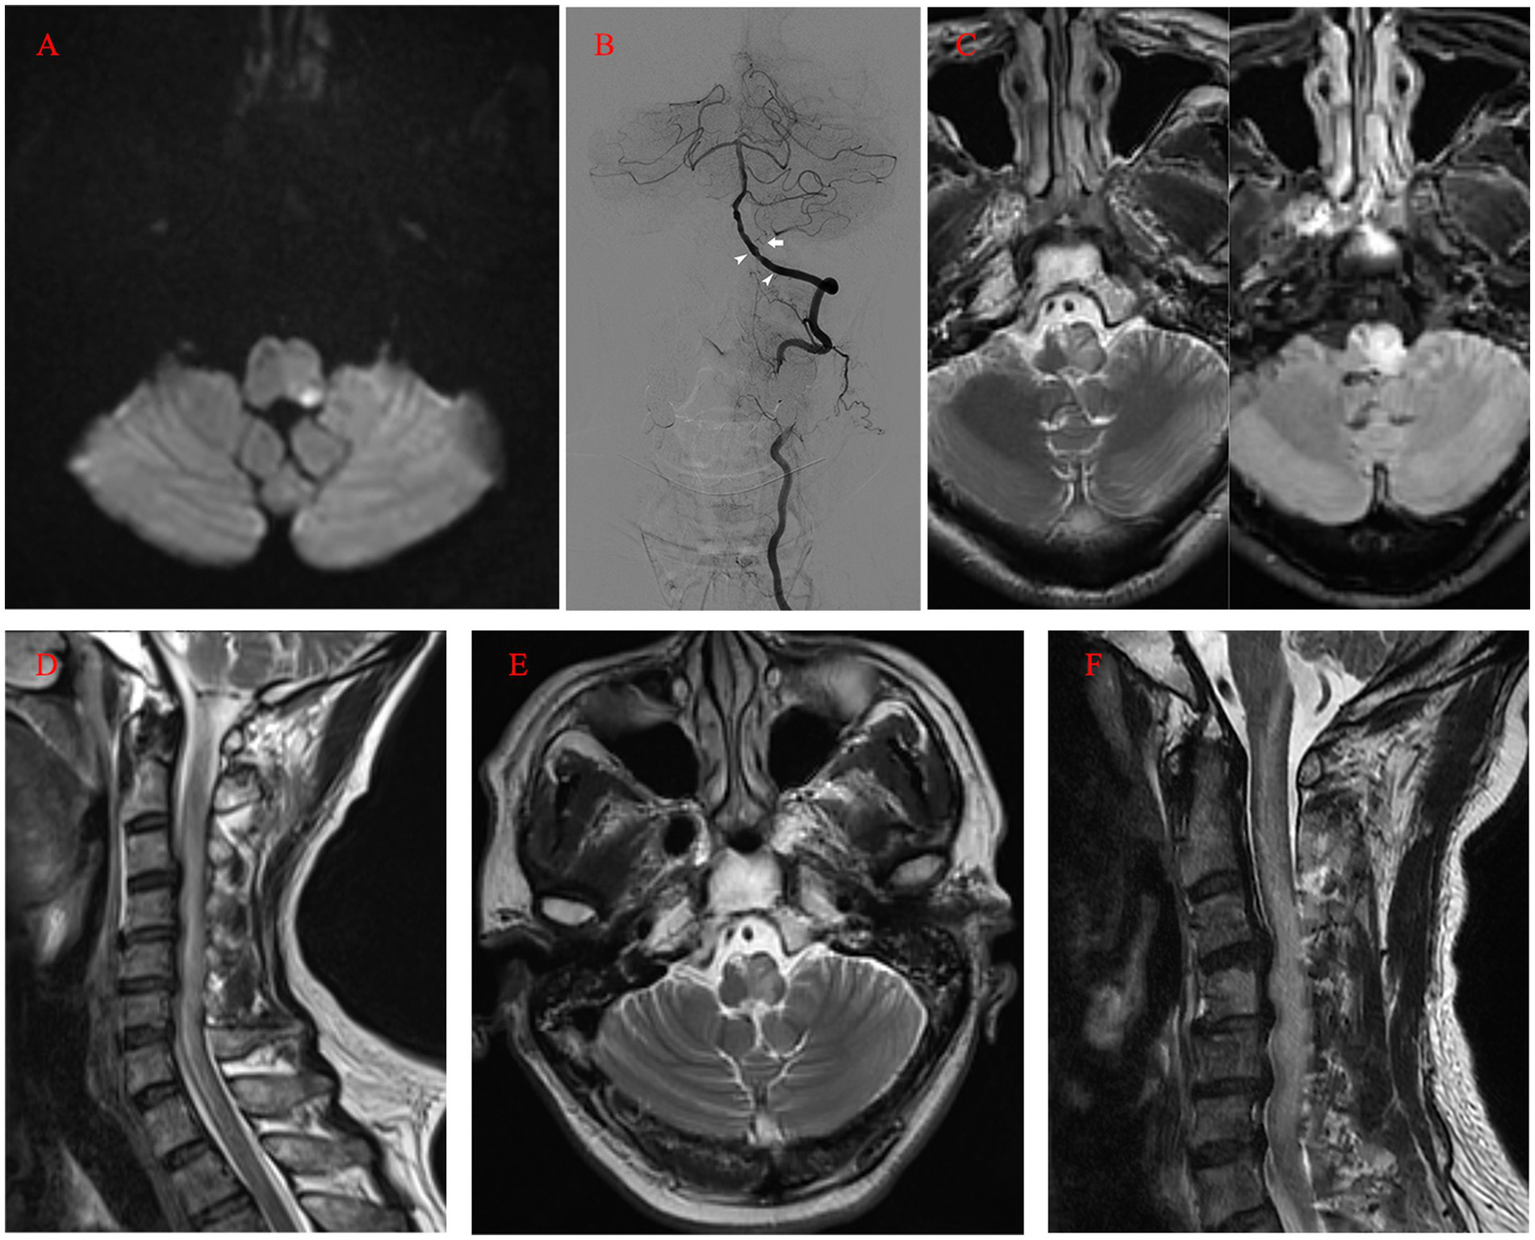

However, at midnight, symptoms worsened, accompanied by dysarthria, left-sided hemiplegia, and elevated blood pressure (around 170/100 mmHg) (Table 1). Again, CT imaging showed no marked changes, while MRI revealed acute infarction of the left posterior medulla oblongata on the next morning (Figure 3A). In addition to the new infarction, T2-weighted and fluid-attenuated inversion recovery (Flair)-weighted images showed newly developed hyperintensity in the left medulla oblongata. Subsequent DSA demonstrated intact vertebrobasilar arteries and patency of the left VA, left PICA, and implanted stent (Figure 3B). To regulate blood pressure, we added an intravenous infusion of esmolol. We used Tirofiban for another 24 h before switching to routine dual antiplatelet treatment with 100 mg aspirin and 75 mg clopidogrel per day. The patient received an intravenous injection of 40 mg methylprednisolone twice per day, along with glycerol fructose and edaravone injections. Three days later, T2 and Flair images showed more profound hyperintensity in the left medulla oblongata (Figure 3C). One day later, a cervical spine MRI (T2 images) revealed unexpected findings of similar hyperintensity and swelling in the cervical cord (Figure 3D). We added an intravenous infusion of mannitol to ameliorate medulla oblongata and cord edema and started early rehabilitation.

Figure 3

(A) MRI (diffusion-weighted imaging) on the first day after the operation showing the acute infarction of the left posterior medulla oblongata. (B) Postoperative angiogram showing the intact vertebrobasilar arteries and patency of the left VA, left PICA (arrow), and implanted stent (arrowhead). (C) MRI (T2 and FLAIR images) on the fourth day after the operation revealing profound hyperintensity in the left medulla oblongata. (D) Cervical spine MRI on the fifth day after the operation revealing similar hyperintensity and swelling in the cervical cord (T2). (E, F) Ten days after the operation, MRI still revealed hyperintensity in the medulla oblongata and cervical cord. MRI, magnetic resonance imaging; VA, Vertebral Artery; PICA, Posterior Inferior Cerebellar Artery; FLAIR, Fluid-Attenuated Inversion Recovery.

Ten days after the operation, MRI still showed marked hyperintensity in the medulla oblongata and cervical cord, while the patient’s symptoms and neurologic deficits gradually improved (Figures 3E,F). The final MRI before discharge showed near-normal intensity in the medulla oblongata and cervical cord, with only slight hyperintensity in the left region. At the 1-year follow-up, MRI showed normal intensity in the medulla oblongata and cervical cord, except for the old lesions (Figures 4A,B). Both VAs remained patent on the CTA (Figure 4C). The patient achieved a favorable outcome, with a modified Rankin scale score of 2. The physical examination revealed normal speech, grade 5 muscle strength in left limbs, and slightly increased muscle tone in the upper left limb.

Figure 4

(A, B) At the 1-year follow-up, MRI (T2) showed normal intensity in the medulla oblongata and cervical cord. (C) Computed tomography angiography revealing the patency of both VAs (arrow). MRI, magnetic resonance imaging; VA, Vertebral Artery.